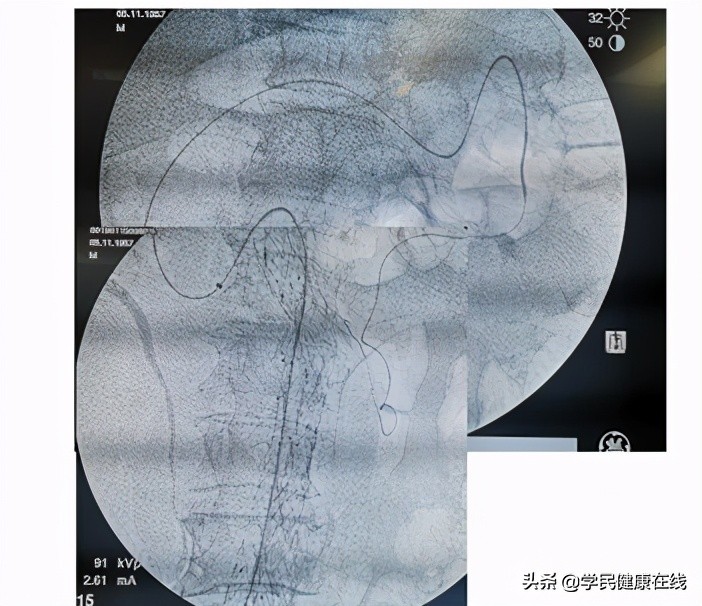

图2.腔内治疗独特的并发症——内漏

从二十世纪八、九十年*开代**始,腔内覆膜支架植入作为腹主动脉瘤的治疗方案逐渐在全世界推广。这一技术是用支架把人工血管支撑在动脉瘤两端的正常血管段,在动脉瘤内重建正常口径的血流通道。这种技术可以把带人造血管的支架压缩在一个圆珠笔杆粗细的管道内,通过大腿根的股动脉,送入体内,在预定位置张开支架。由于术中不需要广泛解剖,可以采用局麻经过腹股沟切口或直接穿刺完成治疗。由于其微创,安全的特点和不高的技术门槛,目前腔内技术已经在一些基层医院得以推广。在更多患者受益的同时,这一技术的特有的并发症累积的数量也逐渐积累、增加,其中最主要的是内漏问题。所谓内漏就是指有持续性血流进入动脉瘤囊内,会导致瘤腔不缩小,甚至继续扩张,部分患者还可以破裂。

腹主动脉瘤腔内隔绝术和开放手术相比,都是重建了血流通道,但是靠支架外撑的力量将人工血管固定在瘤体两端相对正常的血管,而且没有结扎腰动脉和肠系膜下动脉以及骶正中动脉等分支,其独特的并发症的产生和两端固定方式以及术中省略了分支的结扎有关,其中II型内漏就是肠系膜下动脉或腰动脉这些分支血流逆流进入瘤腔。

对II型内漏的处理目前国内都是采用腔内的方式,比如,经过肠系膜上动脉-结肠中动脉-边缘弓-Riolan氏弓-左结肠动脉-肠系膜下动脉,这条路非常迂曲,漫长,到达肠系膜下动脉起始部就可以填塞弹簧圈。去年底,曾经有个病例,由于器材长度不够,而眼睁睁看着,处理不了。